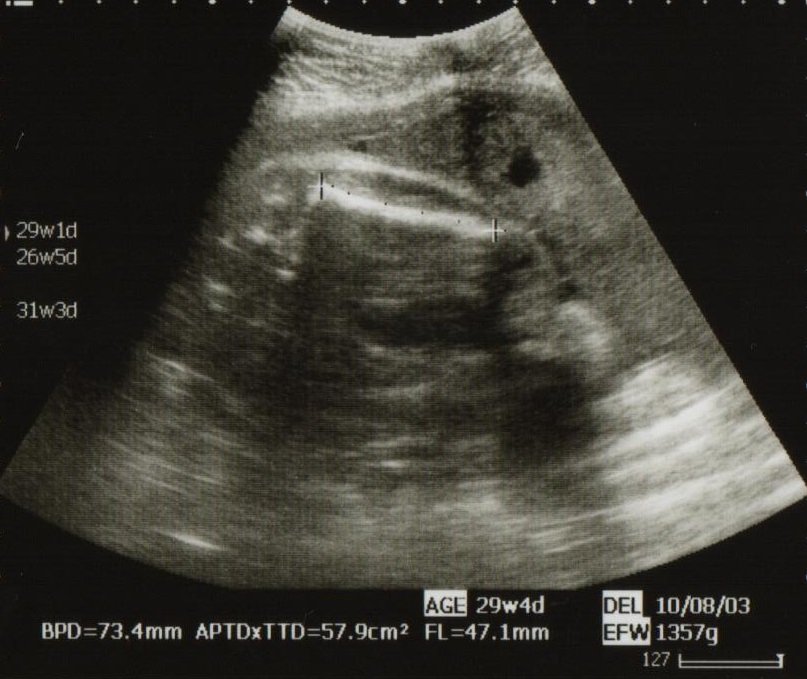

胎児の推定体重(estimated fetal body weight:EFBW)は、次の式で求められる。 EFBW(g)=107×BPD(cm) 3 03×AC(cm) 2 ×FL(cm) 超音波機器に内蔵の推定体重計の判断をします。 胎児発育曲線の± sd の範囲は、正期産・正常体重で生 まれた胎児の約954%が含まれる幅を表しています。(上下に外れるものそれぞ れ23% ) 推定児体重はあくまでも「推定」